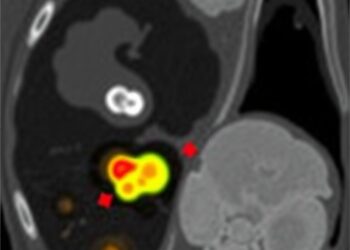

Childhood Rhabdomyosarcoma: Rare Bone Marrow Metastasis Case

In a striking new case report, researchers led by Xiong, T., along with Wan, Q., and Yuan, C., have unveiled ...